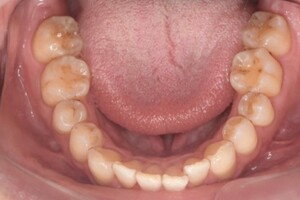

CASE 13

Before

After

基本情報

| 年齢・性別 | 31歳・男性 |

| 主訴 | 歯石をとりたい |

| 治療内容 | スケーリング |

| 治療期間 | 30分 |

| 治療費 | 1,500円(保険診療) |

| リスク・副作用 | 知覚過敏、歯肉退縮 |

| 治療方針 |

定期的なメインテナンスで歯石を除去していきます。 歯石が付くのを予防するため普段から歯間ブラシ、フロスを活用してセルフケアを行ってもらいます。 |